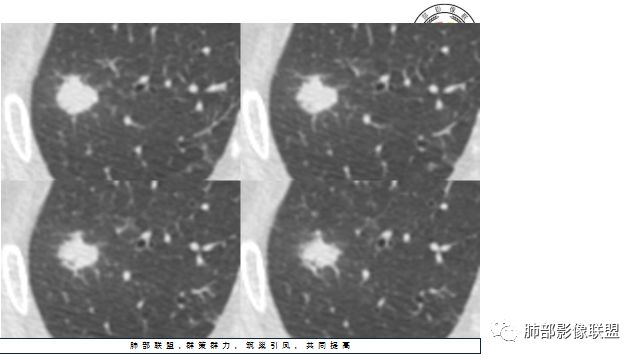

晨读:患者中老年男性,咳嗽 咳痰伴痰中带血2天,发现右上肺结节入院。

胸CT:右上肺结节,病灶位于胸膜下,边缘可见平直 u型征 软毛刺 晕,增强可见延迟强化,病灶中心低密度区。

2.右肺尖类圆形结节影,边界清楚,未见明显分叶或深切迹,部分分边缘较平直,可见细长毛刺棘状突起,相邻胸膜增厚,未见胸膜凹陷。后段胸膜下见条索影及微小结节影。

相关血管未见脐凹,有限图像层面未能显示相关支气管情况。

3.平扫病灶密度密度不甚均匀,外侧份见微小高密度影。